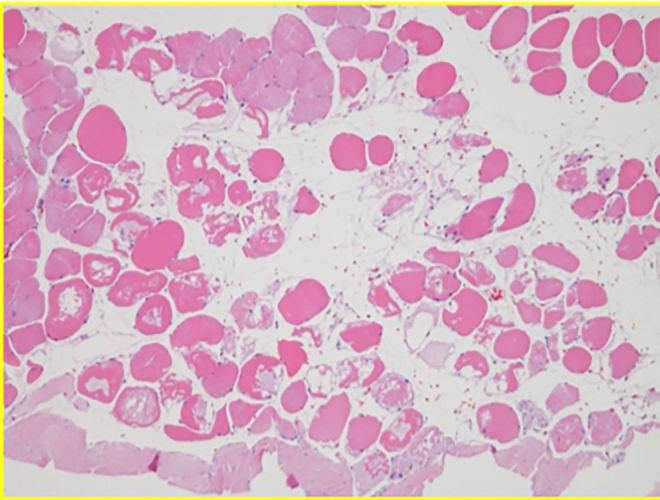

Histology

No necrosis, no infection